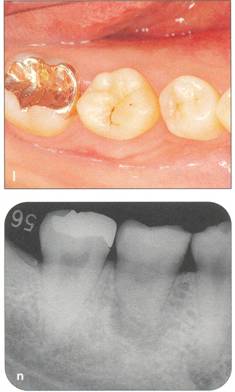

Fi 545e45f g 5-4f Extracted second molar, which will be discarded. Fi 545e45f g Extracted donor tooth. The amount of periodontalligament is adequate. Transplantation was performed 6 weeks after extraction of the tooth from the recipient site. Fi 545e45f g 5-4h View of the donor site and preparation of the recipient site. |

Fi 545e45f g 5-4i After the gingival flap has been sutured and the donor tooth has been splinted. The distal aspect of the donor tooth is closed as tightly as possible. Fi 545e45f g 5-4j After transplantation. Fi 545e45f g 5-4k Two weeks after trans plantation |

Fi 545e45f g 5-41 Six weeks after transplantation. The root canals have been cleaned, shaped, and filled with calcium hydroxide. Fi 545e45f g 5-4m Three months after transplantation. The radiograph was taken after removing the splint. Fi 545e45f g 5-4n Seven months after transplantation. |

Fi 545e45f g 5-40 Seven months after transplantation. Mesial migration of the donor tooth and regeneration of alveolar bone can be observed. Fi 545e45f g 5-4p One year after transplantation. Fi 545e45f g 5-4q Two years after transplantation. |